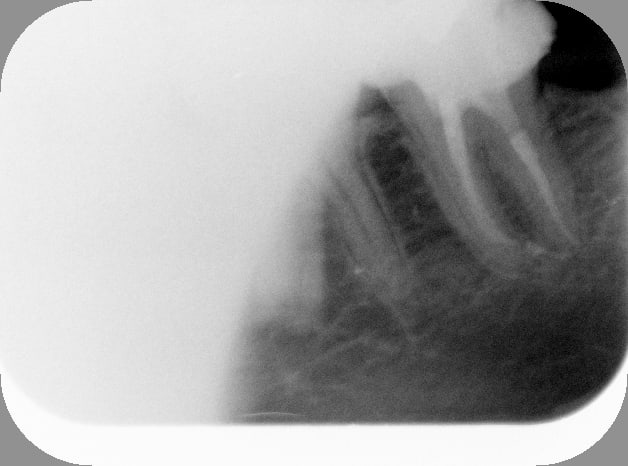

Avant t89ni5 - Eugenol